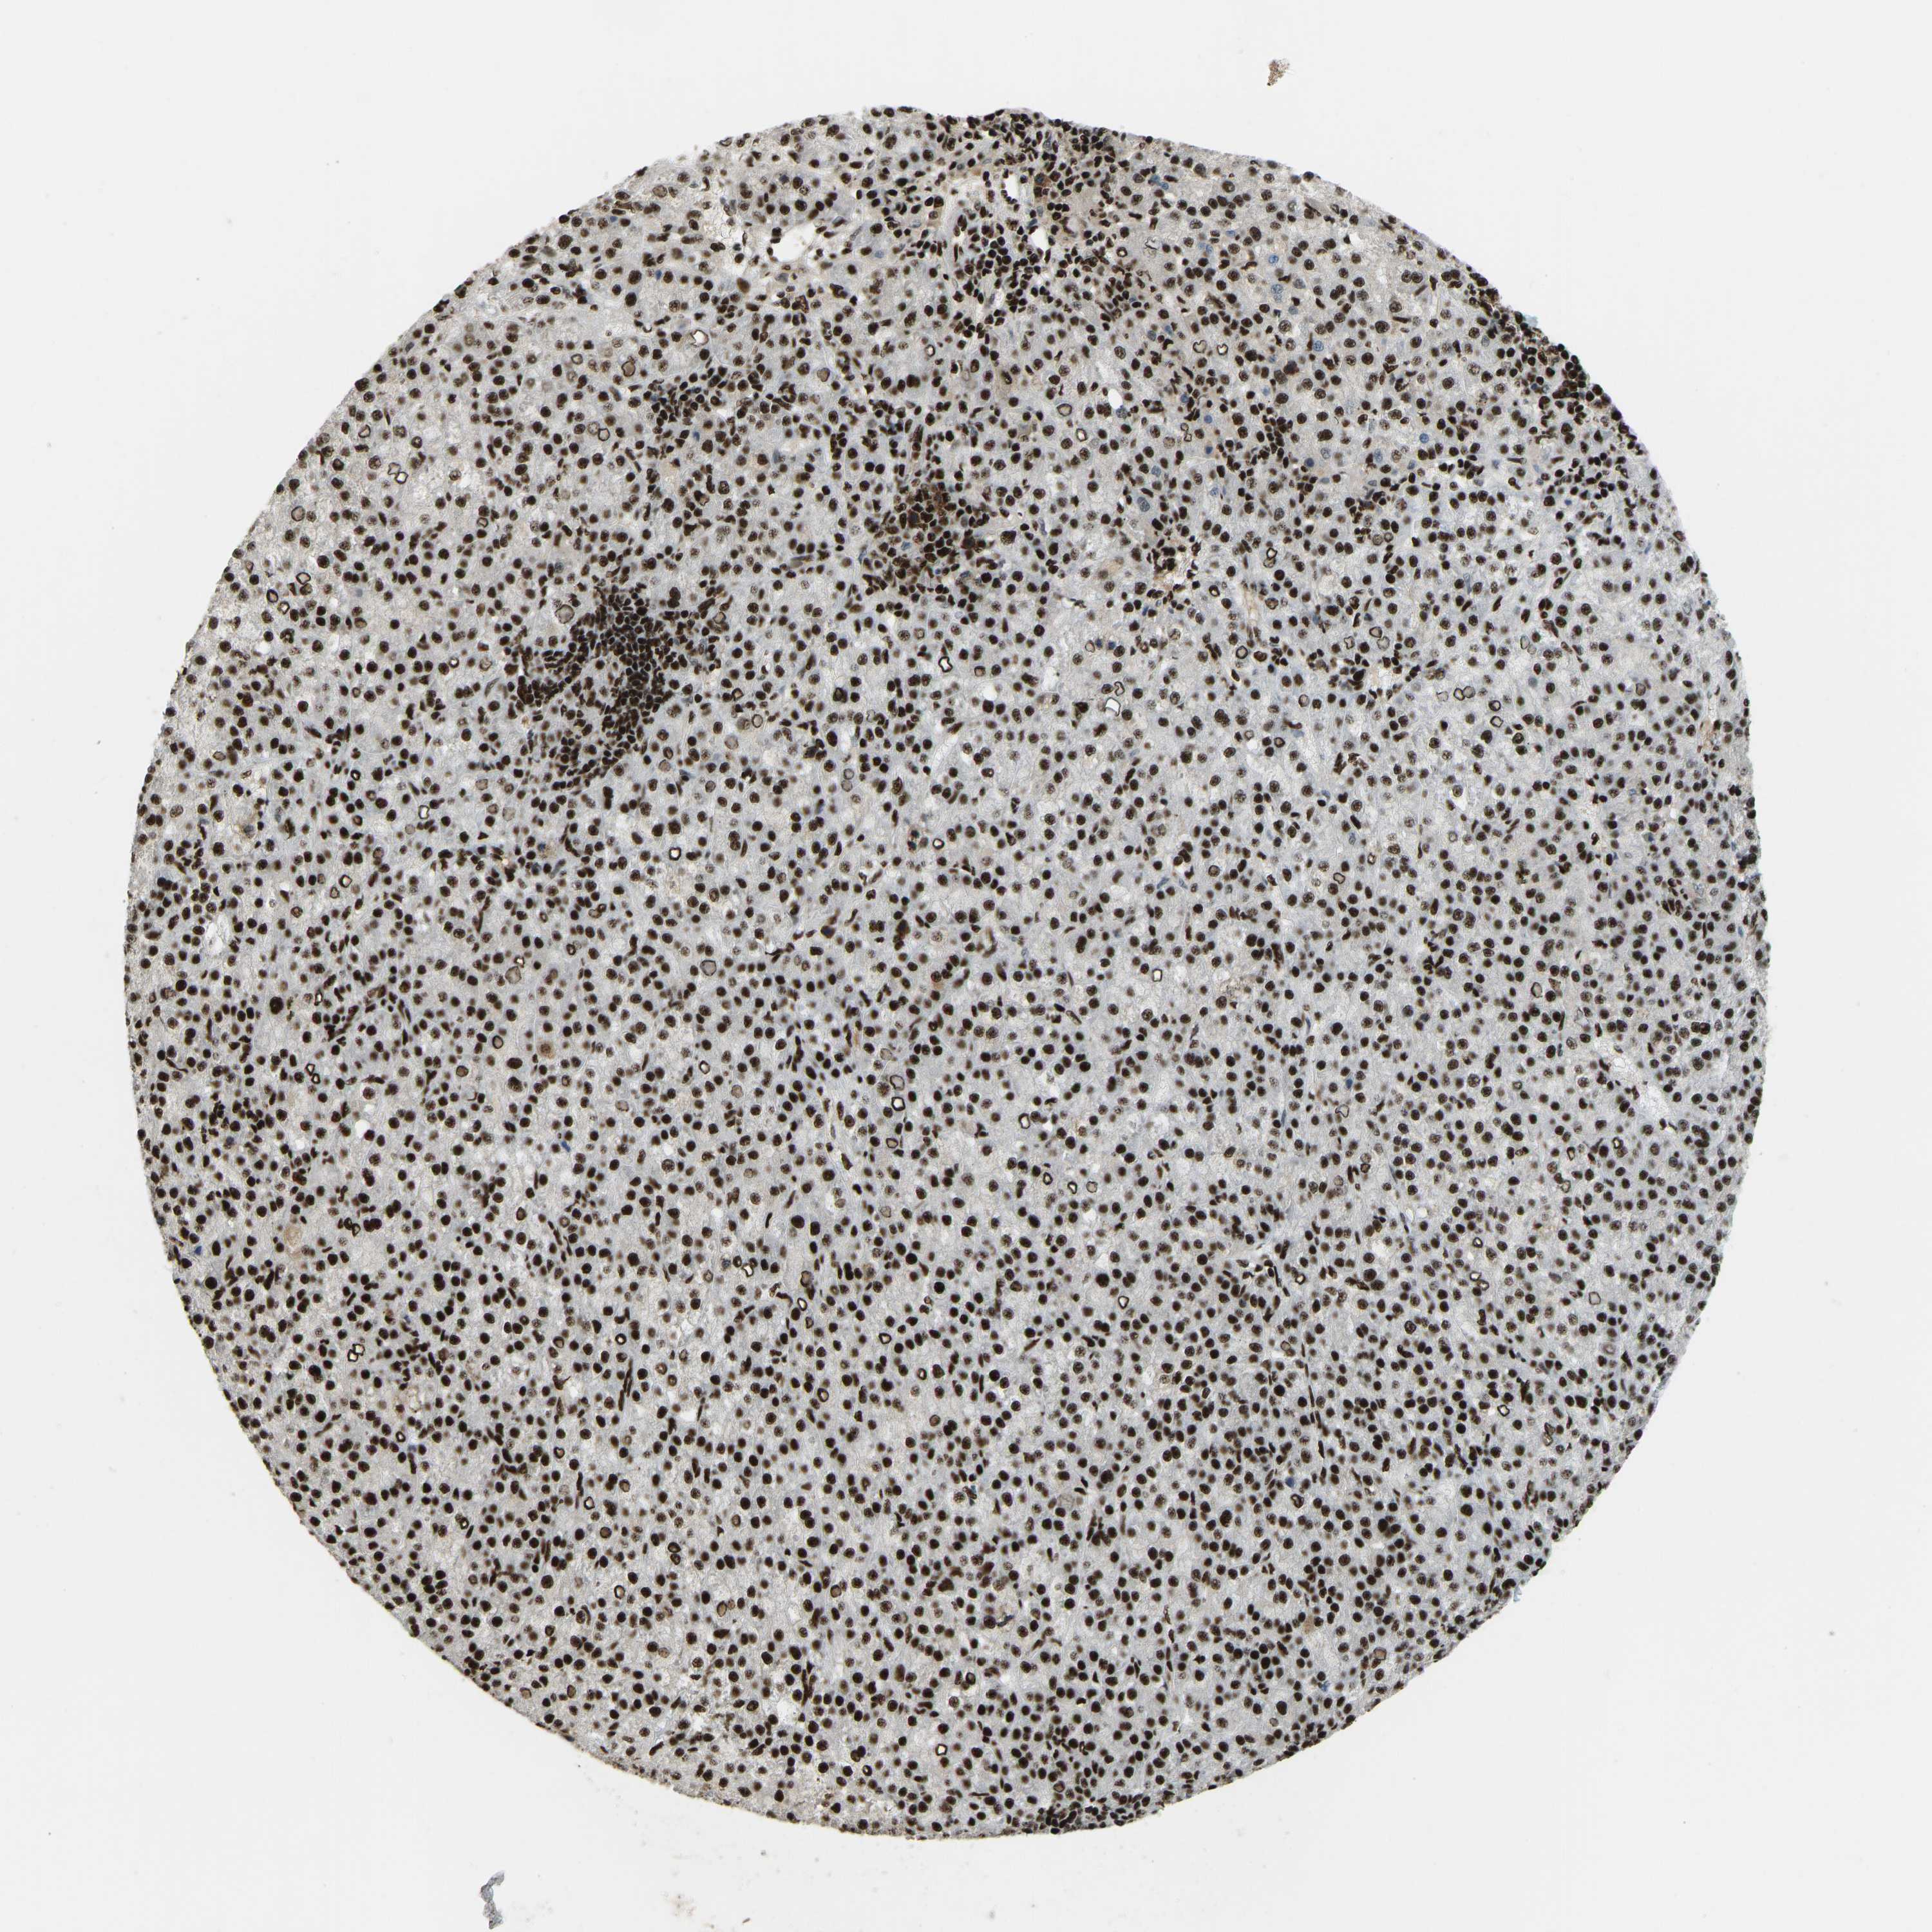

LIVER CANCER - Protein expressioni

A mouse-over function shows sample information and annotation data. Click on an image to view it in a full screen mode. Samples can be filtered based on level of antibody staining by selecting one or several of the following categories: high, medium, low and not detected. The assay and annotation is described here.

Note that samples used for immunohistochemistry by the Human Protein Atlas do not correspond to samples in the TCGA dataset.

Antibody stainingi

Antibody staining in the annotated cell types in the current human tissue is reported as not detected, low, medium, or high, based on conventional immunohistochemistry profiling in selected tissues. This score is based on the combination of the staining intensity and fraction of stained cells.

Each image is clickable and will lead to virtual microscopy that enables deeper exploration of all samples and also displays staining intensity scores, fraction scores and subcellular localization as well as patient and tissue information for each sample.

Antibody HPA017998

Antibody HPA018864

Staining

High

Medium

Low

Not detected

Intensity

Strong

Moderate

Weak

Negative

Quantity

>75%

75%-25%

<25%

None

Location

Nuclear

Cytoplasmic/membranous

Cytoplasmic/membranous,nuclear

Cholangiocarcinoma

Carcinoma, Hepatocellular, NOS